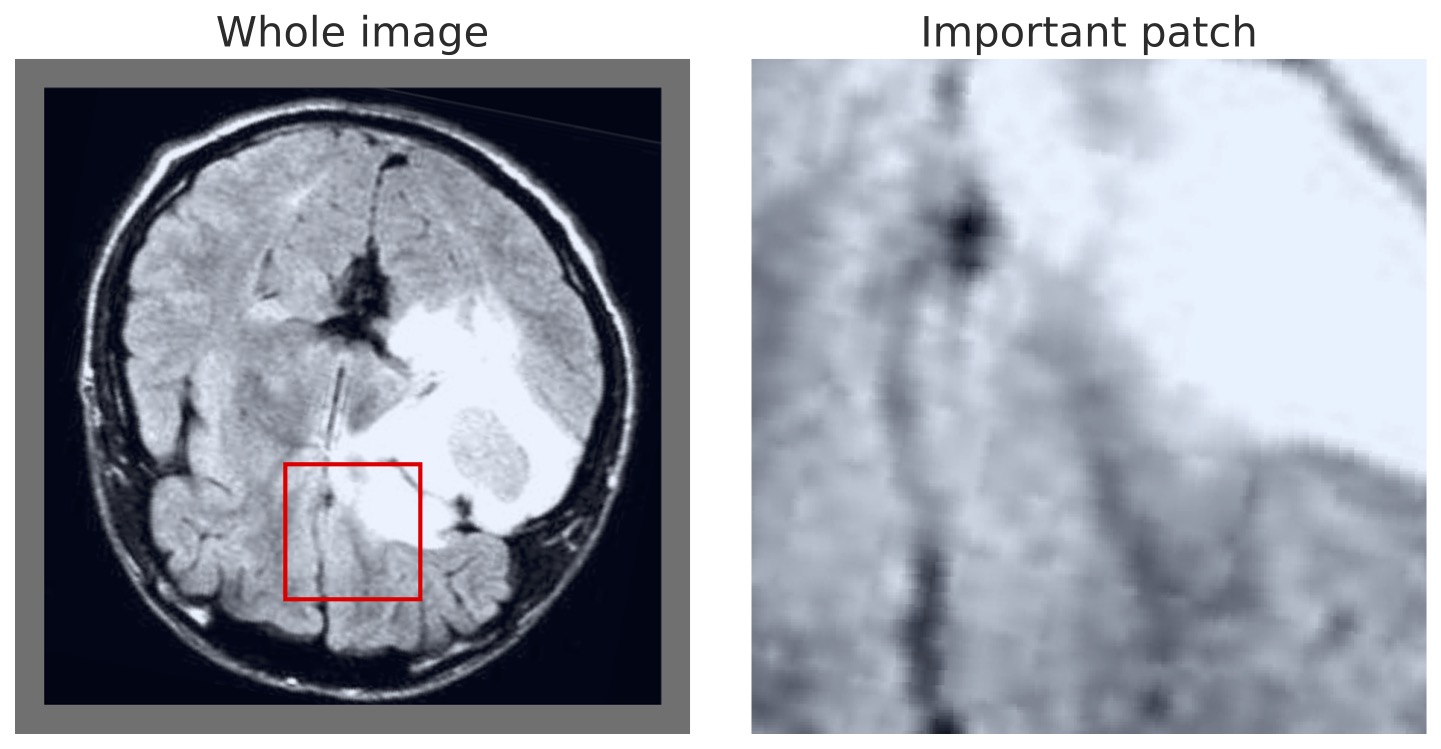

A further benefit of our approach is that the concept vectors can be used to gain an interpretable component about what the model is learning to look for. We can do this by showing example patches that correspond to the ’th concept vector activating and having the maximal response, i.e., making the classification determination. We provide an example for the first five concept classes on the BTMD dataset in Figure 4 and the RSNA-SMBC dataset in Figure 5. In both cases, the row corresponds to a concept, and 25 columns show 25 winning exemplars.

The BTMD dataset has considerably more visual variation in the images, making them more challenging to inspect as non-medical experts, but visual themes are generally discernible across each row in Figure 4. We note that there is no mechanism to force one concept vector to suppress other concept vectors for similar activations, and so we see some cross-pollination between the concept vectors. The RSNA dataset has less visual asperity, and visual patterns are more clearly observed in the rows of Figure 5.

In Figures 7 and 8, we display more representative patches selects that correspond highly to a given concept vector (one concept per row), highlighting our our method automatically learns sub-regions of the larger image space.